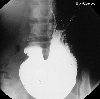

A case of a metastatic gastric tumor originating from breast carcinoma.

X-ray